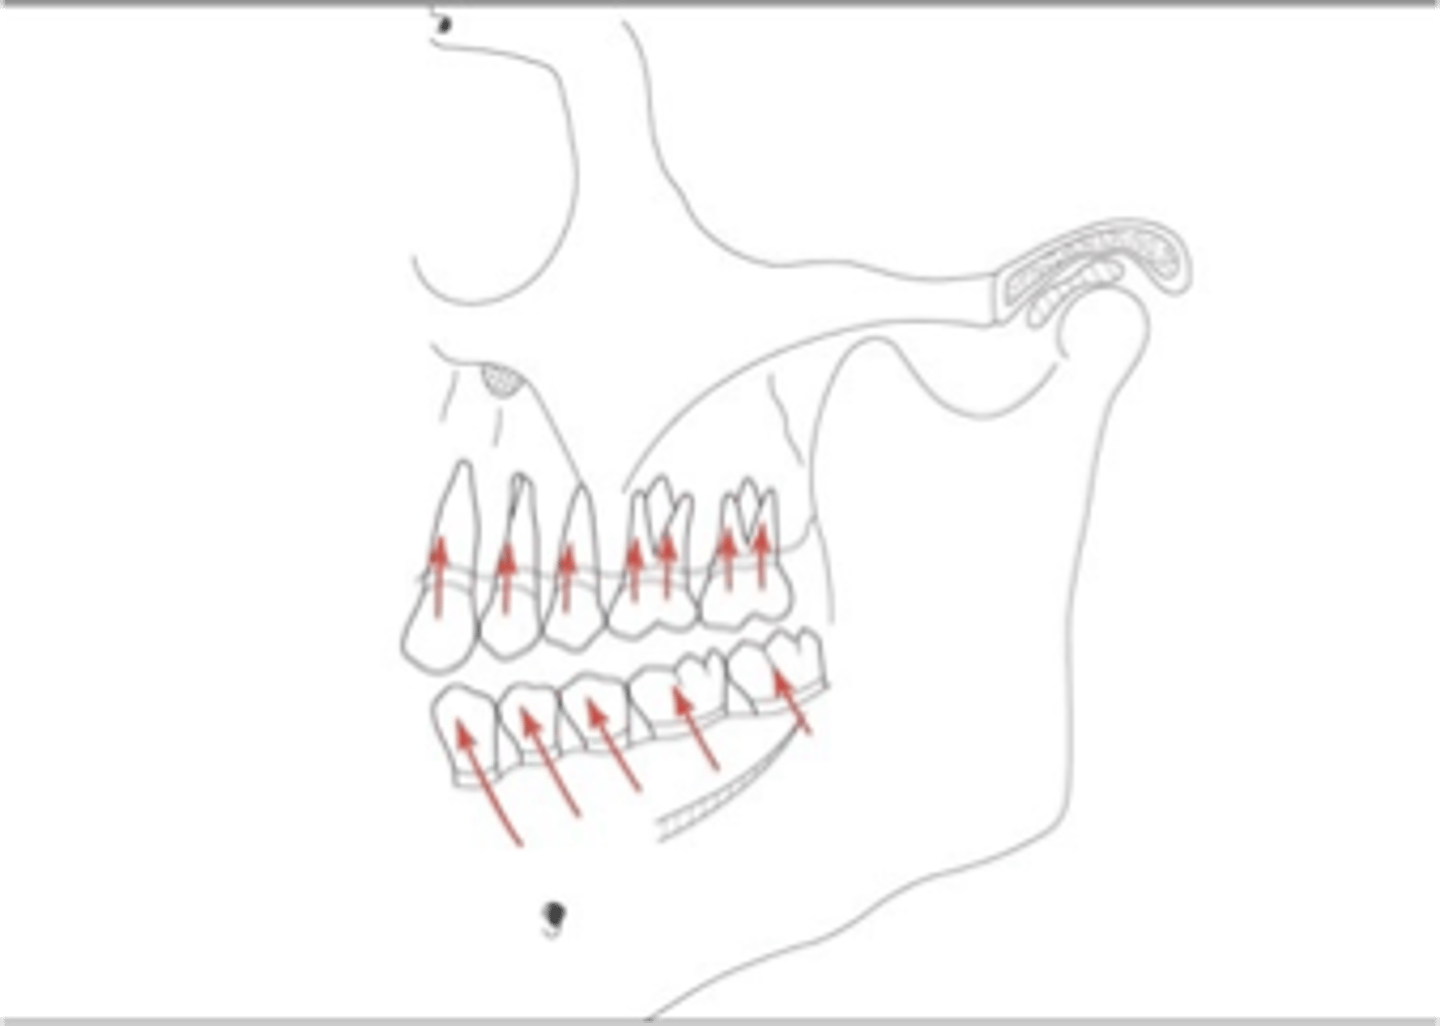

axial loading

In well-aligned, intact dental arches, teeth and periodontium sustain mostly ...

axially directed force

Response of dento-alveolar tissues respond better to which type of directed force

support during function

The goal of any prosthesis is to provide ________to mimic that in natural dentition.